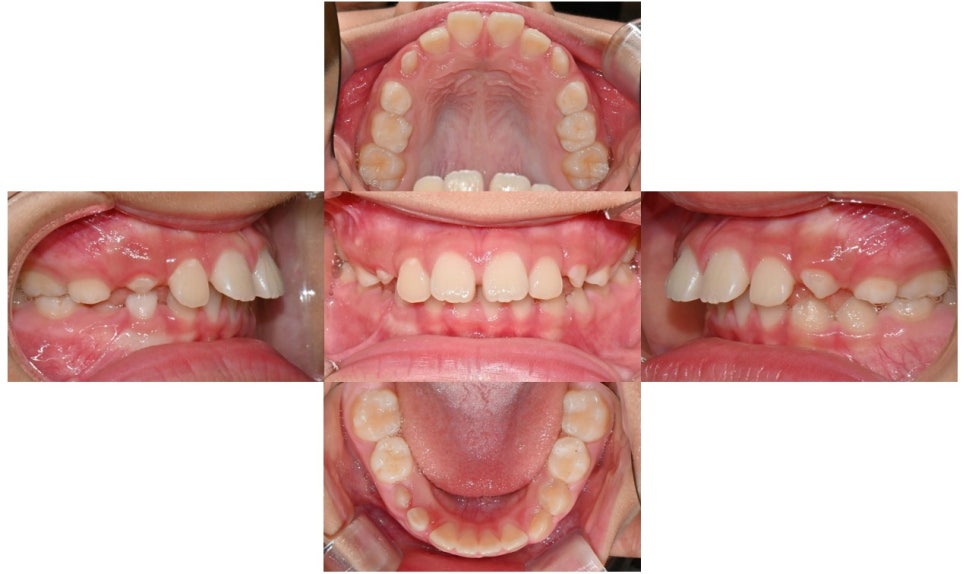

본 환자는 앞니가 점점 돌출된다는 주소로 치과에 내원하였으며, 앞니가 많이 뻗쳐있었고 과개교합 양상도 보였습니다. 또한 어금니 위치 관계도 2급(아래 어금니가 뒤로 후퇴하여 물리는 위치 관계) 이었습니다.

2024.8.3. 초진

편안하게 입술을 다물었을 때 후퇴된 아래턱 및 돌출된 위 앞니가 하순에 닿아 눌러서 아래턱은 후퇴되어 있음에도 아래 입술은 오히려 돌출감이 있었습니다.